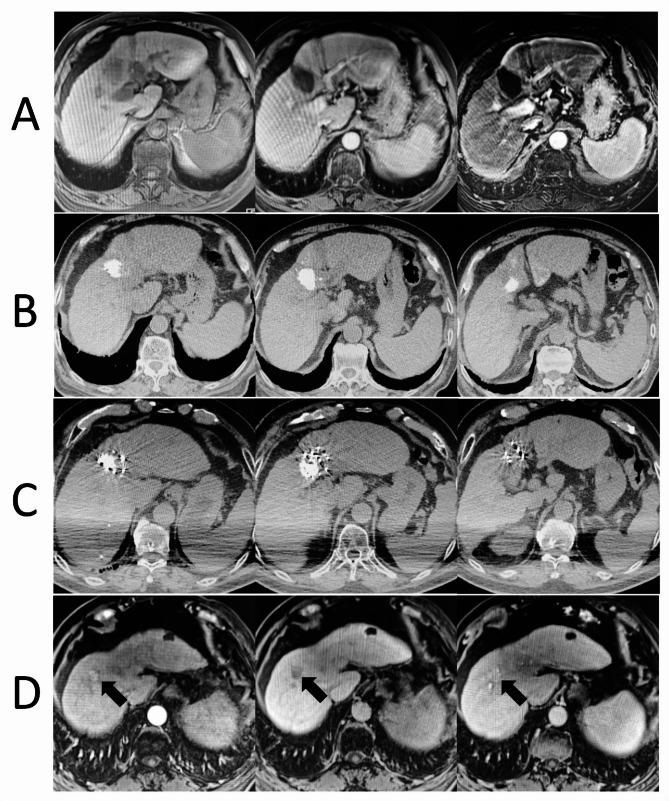

Methods: A retrospective analysis of 71 patients (57 males, 14 females, median age 64) treated at three Chinese hospitals from 2018 to 2024 was conducted. The main outcomes were local progression-free survival (LPFS) and overall survival (OS). Treatment involved a 16-slice Spiral CT and Radioactive Particle Treatment Planning System (TPS), with seeds of 18.5-29.6 MBq implanted via freehand puncture. Efficacy was evaluated using the modified Response Evaluation Criteria in Solid Tumors (mRECIST) at three months, with follow-ups every three months for three years, then biannually until December 2024. Data analysis utilized SPSS 22.0, Kaplan-Meier, and Cox models.

Results: With a median follow-up of 37 months, the complete response (CR) rate was 57.7%, partial response (PR) 31.0%, stable disease (SD) 5.6%, and progressive disease (PD) 5.6%. Local control was 94.3%. LPFS rates at 1, 3, and 5 years were 74.6%, 29.5%, and 1.4% (median LPFS 22 months), while overall survival (OS) rates were 88.7%, 47.8%, and 12.6% (median OS 35 months). CR was a key protective factor for LPFS and OS. Significant factors included the Barcelona Clinic Liver Cancer (BCLC) stage C, intrahepatic progression, and extrahepatic metastasis. Postoperative complications occurred in 35.2% of patients, with no severe cases.